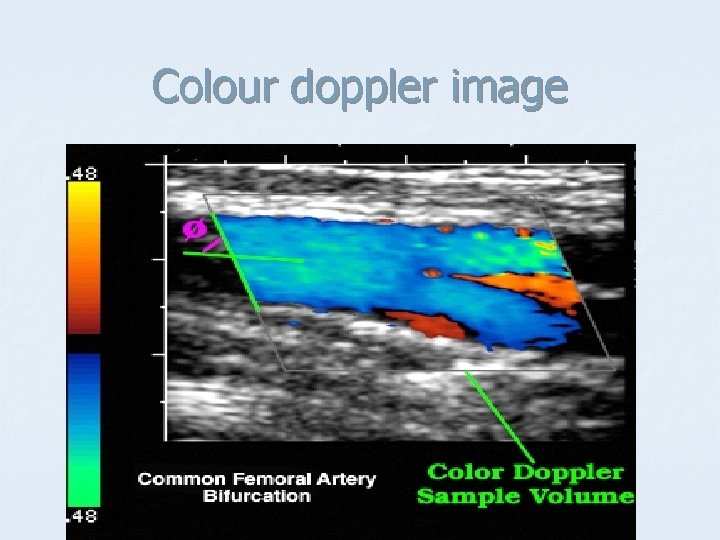

Doppler Mode. - Includes the capability of accurately measuring velocities of moving material, such as blood in arteries and veins. The principle is the same as that used in radar guns that measure the speed of a car on the highway. - Doppler capability is most often combined with Bmode scanning to produce images of blood vessels from which blood flow can be directly measured. - This technique is used extensively to investigate valve defects, arteriosclerosis and hypertension, particularly in the heart, but also in the abdominal aorta and the portal vein of the liver.

Colour doppler image

Colour doppler –Duplex